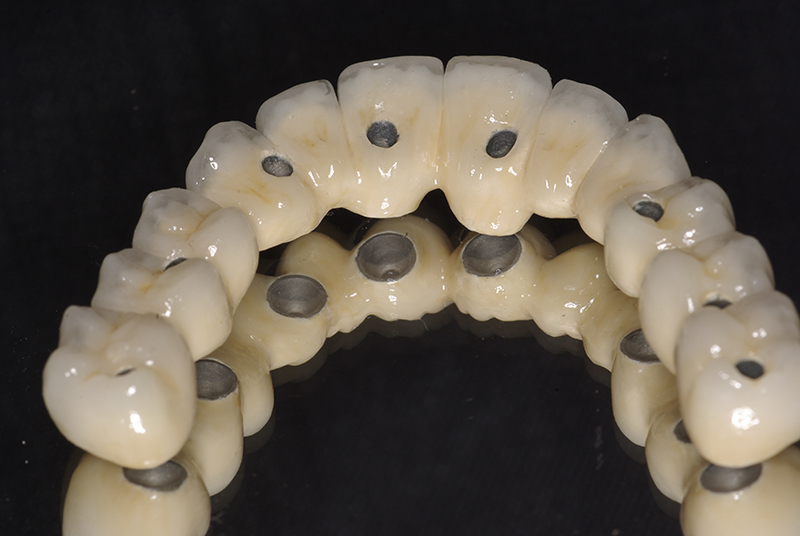

- Fixação da Prótese: Em até 72 horas após a cirurgia, a prótese provisória é instalada, permitindo que o paciente recupere a funcionalidade e a estética imediatamente.

- Conforto e Estética: A prótese provisória é funcional e visualmente semelhante aos dentes naturais.